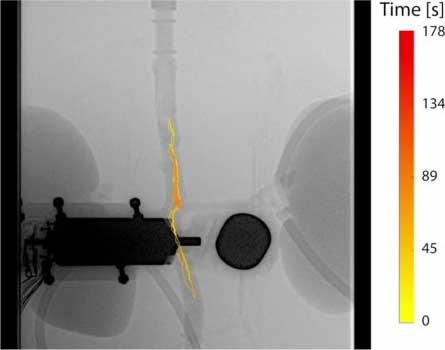

For the experiment, the researchers used a rotating magnet controlled by a robotic arm to send the millirobots wirelessly through the blood vessel. They used an X-ray machine to locate the millirobots as they swam through the aorta. The researchers used a maximum blood flow in the aorta of 120 ml per minute. But with a stronger magnet, the millirobots can swim through a stronger current. The millirobots swam stable straight stretches with the current and against the current. This was possible with one, but also with several millirobots at the same time.